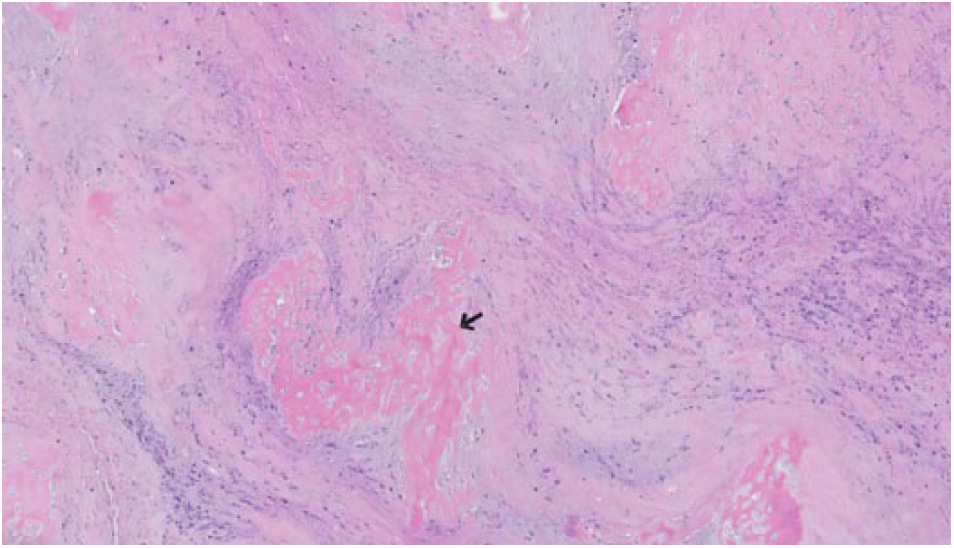

The microscopic examination of the kidney tumor revealed sheets of atypical spindle cells with abnormal mitotic figures, nuclear pleomorphism, and areas of necrosis compatible with sRCC (Figure 3) with osseous metaplasia (Figure 4). The tumor disrupted the renal capsule and extended to the posterior tissue resection edge. A hilar lymph node was positive for metastatic carcinoma. The metastatic tumor showed papillary architecture with abundant eosinophilic cytoplasm, high-grade nuclei, prominent nucleoli with necrosis, and psammoma bodies consistent with type 2 (eosinophilic) PRCC (Figure 5). The RCC tumor thrombus and venous and lymphatic invasion were identified. Ureterovascular margins were negative for malignancy. The adrenal gland, spleen, pancreas, and bowel were also negative for malignancy.

Osseous metaplasia (arrow).